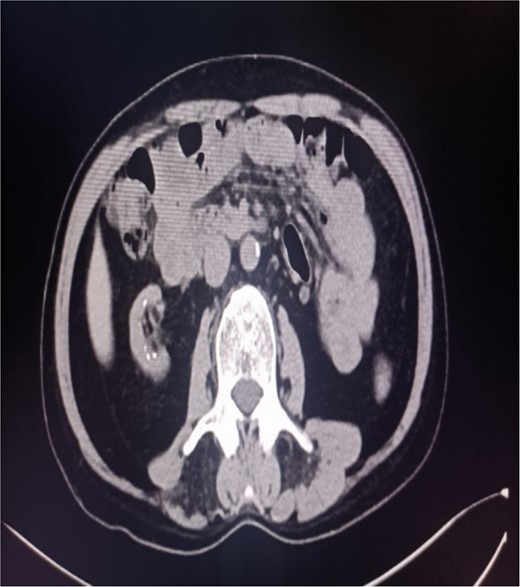

Abdominal CT showing multiple punctate stones in the right renal area in situ.

A 39-year-old man with kidney stones after kidney transplantation was admitted to our hospital on 29 November 2023. Eight years ago, he underwent a kidney transplant from a donor. Neither the donor nor the recipient had a history of kidney stones. The transplanted kidney was positioned in the right iliac fossa, and the patient had a successful postoperative recovery. However, a recent routine abdominal computed tomography (CT) scan revealed multiple stones in the transplanted kidney and bilateral in situ kidney atrophy. The stone was located in the lower calyx of the transplanted kidneys. Hydronephrosis was also observed. Kidney, ureter, and bladder radiographs showed multiple high-density speckles in the right kidney, the largest of which was ~0.5 cm in diameter. Physical examination (blood pressure, 147/91 mmHg; serum creatinine, 72.7 μmol/L; urea nitrogen, 5.1 mmol/L) revealed normal liver function, coagulation, and electrolytes. We suspected that these kidney stones were sizable and necessitated surgical intervention. Upon admission, pertinent examinations were conducted, and preoperative preparations were completed.